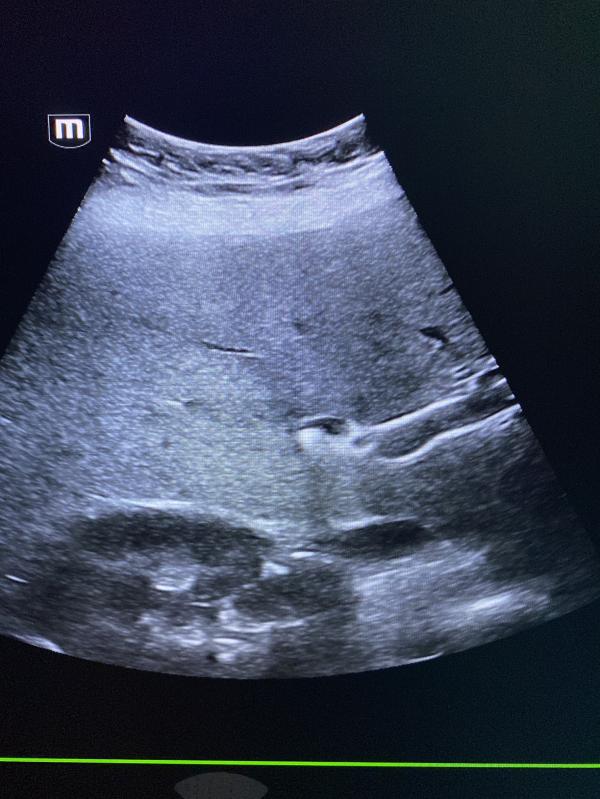

В течении 4 дней девушку беспокоили боли. Не могли установить причину.

Камень в холедохе ( в общем жёлчном протоке).

Дополнительно реактивные изменения в поджелудочной железе.

Жёлчный пузырь удален 3 года назад.

В данном случае пациентка мучалась от боли, неоднократно проводили узи в стационарах города , заключение не выдавали 🤕. Хирурги требовали заключение УЗИ .